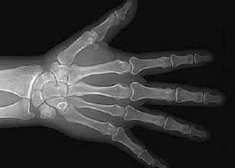

11 August 2005 A South African device originally designed to detect the theft of diamonds by mineworkers is saving the lives of critically injured patients around the world. Taking just 13 seconds to provide a full-body x-ray, the Lodox Statscan saves time during the vital "golden hour." "It is an innovation designed in South Africa, for South Africa," says Lodox product manager Rodney Sandwith. Sandwith received the Chairperson's Award for the Statscan at the SABS Disa Design Institute Awards in May - the most recent in a succession of awards since the product was first unveiled in 2003. The Statscan is able to provide scans of both bone and soft tissue, useful in the diagnosis of a wide range of traumatic injuries. The full body overview means injuries can be quickly identified. "We can use it to make high quality x-rays of the entire body or just a hand. It represents the safest choice for doctors before deciding to use expensive high-dose CT or other scans," says Sandwith. This versatility gives the scanner an edge over many other imaging technologies. The open design of the device also means that medical personnel have access to critically injured patients at all times during scanning. The images are digital, so they can be transferred across the hospital's computer network, rotated and manipulated without any loss of quality. There is also no need for x-ray film or cartridges, dramatically reducing operating costs. A study conducted at the trauma unit at Groote Schuur Hospital in Cape Town over more than two years found that the Statscan offered significant improvements in patient handling, reducing the time required to complete a diagnostic examination from 48 to five minutes. The same study also showed that both patients and medical staff were exposed to significantly lower radiation doses compared to conventional x-ray devices. The technology at the core of the Statscan was developed for security purposes for De Beers' diamond mines. When the humanitarian possibilities of the scanner became apparent, De Beers became one of the primary investors in the Lodox consortium. The other primary backers are the Industrial Development Corporation and emergency services provider Netcare. The company has recently been awarded a contract to supply the Sudanese government with four Statscans at a total cost of US$1.2-million. The Statscan is already in use in 10 US hospitals, and has received full approval from the US Food and Drug Administration. "It is a state-of-the-art, lifesaving medical system," says Sandwith. "A technology all South Africans can be proud of." SouthAfrica.info reporter

The Statscan is able to provide full body imagery, and close ups The Statscan is able to provide both full-body imagery and close-ups (Photo: Lodox) A full body X-ray in just 13 seconds Medical personnel have full access to the patient during the scan (Photo: Lodox)